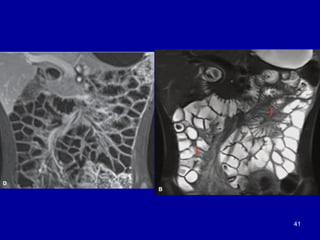

CT and MRI enterography

• Improves up on barium study by demonstrating extra luminal

compartment, mesentery, solid organs, peritoneum &

retroperitonium

• MRE is used mostly in the initial diagnosis and follow-up of

inflammatory bowel disease; CTE is used for small bowel

lesions

• Contrast administration can be performed perorally (i.e., CT /

MR enterography) or by infusion via nasoenteric intubation

(i.e., CT/MR enteroclysis)

• Neutral or positive oral contrast can be used

CT enterography cont..

• Patients drink approximately 1.5–2 L of oral contrast over

45–60 min

• 150 ml of Iohexol (Omnipaque 300) administered intravenously

• Neutral or low-density oral contrast media are a prerequisite

for good-quality CT enterography

ü Water–methylcellulose solution,

ü lactulose solution,

ü polyethylene glycol,

ü low-density barium, 0.1% w/v Volumen and

ü milk

39

bowel is distended with

low-attenuation

methylcellulose given

orally

40

CT and MRIenterography • Improves up on barium study by demonstrating extra luminal compartment, mesentery, solid organs, peritoneum & retroperitonium • MRE is used mostly in the initial diagnosis and follow-up of inflammatory bowel disease; CTE is used for small bowel lesions • Contrast administration can be performed perorally (i.e., CT / MR enterography) or by infusion via nasoenteric intubation (i.e., CT/MR enteroclysis) • Neutral or positive oral contrast can be used 38

CT enterography cont.. •Patients drink approximately 1.5–2 L of oral contrast over 45–60 min • 150 ml of Iohexol (Omnipaque 300) administered intravenously • Neutral or low-density oral contrast media are a prerequisite for good-quality CT enterography ü Water–methylcellulose solution, ü lactulose solution, ü polyethylene glycol, ü low-density barium, 0.1% w/v Volumen and ü milk 39

bowel is distendedwith low-attenuation methylcellulose given orally 40